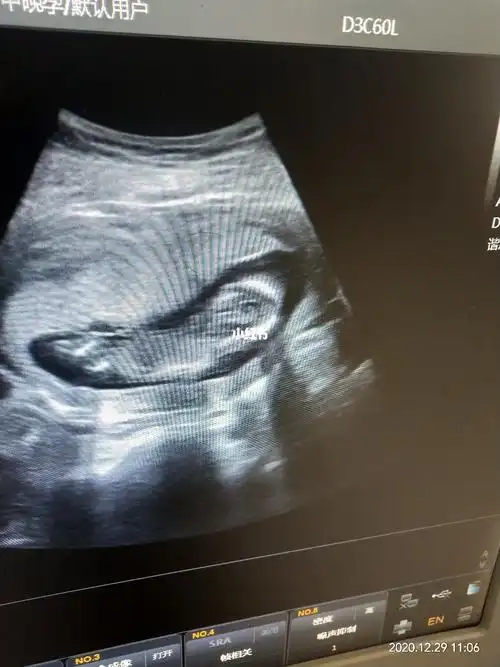

宝宝孕16周了,一切检查秒过,健康男孩宝一枚,儿女双全太幸福了

▼16周大的胎儿 小家伙用手探索自己的身体以及周围的环境